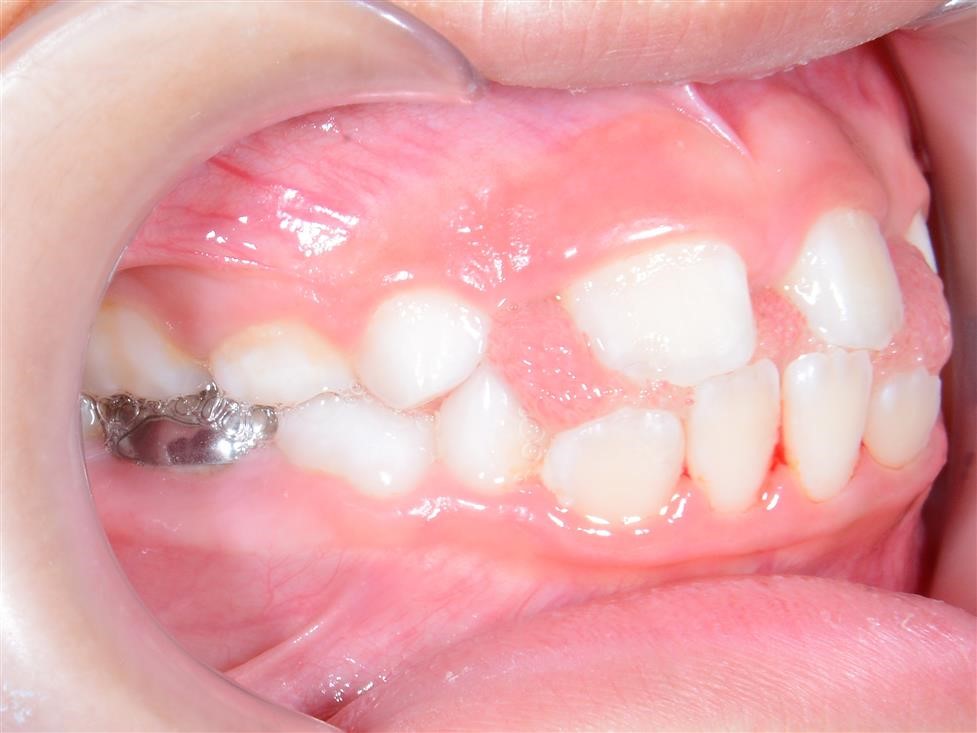

Chức năng cắn: Những răng không được tiếp xúc tốt với răng tương ứng ở hàm đối diện có thể gây khó khăn khi ăn uống và có thể dẫn tới rối loạn chức năng khớp thái dương- hàm. Tuy nhiên, mối liên hệ giữa rối loạn chức năng khớp thái dương hàm và lệch lạc khớp cắn vẫn là một vấn đề gây tranh cãi. Những cá nhân có khớp cắn không tốt, có thể cảm thấy khó khăn và ngượng ngùng khi ăn vì họ không thể cắn được miếng thức ăn bằng răng cửa của mình. Họ chỉ có thể nhai thức ăn bằng những răng phía sau. Sức khỏe răng miệng: Vệ sinh răng miệng trở nên khó khăn hơn. răng dễ có mảng bám và cao răng hơn nếu hàm răng khấp khểnh không đều. Do vậy, bệnh nhân có thể dễ bị sâu răng và các bệnh nha chu khác như viêm lợi và viêm quanh răng hơn. Tuy nhiên, nếu có một hàm răng đều đặn mà không có ý thức và thực hành vệ sinh răng miệng tốt thì cũng không thể có tình trạng vệ sinh răng miệng tốt. Nếu chải răng không đầy đủ và không đúng cách, các bệnh nha chu sẽ tiến triển bất chấp hàm răng của họ thẳng đều đến mức nào. Trong nhiều trường hợp lệch lạc khớp cắn có thể làm tổn thương cả răng và mô mềm nếu không được điều trị. Hiển nhiên rằng răng cửa hàm trên càng chìa ra nhiều bao nhiêu thì nó lại càng dễ bị tổn thương bấy nhiêu. Khi khoảng cách theo chiều ngang giữa răng cửa hàm trên và răng cửa hàm dưới là 9mm hoặc lớn hơn, nguy cơ tổn thương răng cửa hàm trên tăng lên tới hơn 40%. Giảm độ chìa ra của răng cửa hàm trên không chỉ có lợi ích trên quan điểm thẩm mỹ mà còn hạn chế tối đa nguy cơ chấn thương và sự phức tạp về lâu về dài cho cả hàm răng. Những tình trạng khớp cắn ngược, không chỉ ảnh hưởng nhiều đến vấn đề thẩm mỹ mà còn ảnh hưởng đến chức năng cắn và gây ra tình trạng mòn răng – răng sớm, răng cửa dưới bị tiêu xương ổ răng, lợi bị co…Trong trường hợp được điều trị sớm, tổn thương mô mềm sẽ dừng lại và khi phần lợi còn lại được tái tạo thì tình trạng sẽ được cải thiện một cách tự nhiên và không để lại vấn đề gì sau này.

Khớp cắn chéo quá sâu có thể tình cờ gây ra loét mô mềm, những trường hợp này nhu cầu thẩm mỹ thì nhỏ nhưng vấn đề loại bỏ nguyên nhân gây chấn thương mô mềm thì lớn. Ai nên được điều trị chỉnh nha? Phần lớn điều trị chỉnh nha được tiến hành vì nhu cầu thẩm mỹ và lợi ích mà mỗi bệnh nhân nhận được từ việc điều trị sẽ phụ thuộc vào mức độ trầm trọng của mức độ sai khớp cắn và nhận thức của bệnh nhân về vấn đề này. Một số cá nhân có thể có sự lệch lạc ở mức độ quá rõ ràng làm ảnh hưởng trầm trọng tới gương mặt của họ tuy nhiên họ cũng chẳng quan tâm đến và không cần điều trị nếu bác sỹ không có cách thuyết phục. Bác sĩ lâm sàng có thể đưa ra lời khuyên về phương pháp điều trị cho bệnh nhân nhưng cũng không nên yêu cầu họ một cách cứng nhắc mà nên để cho họ có thời gian ngồi lại và suy nghĩ để đưa ra quyết định cuối cùng hợp tác với bác sỹ điều trị. Lệch lạc khớp cắn mức độ nhẹ nên được điều trị với sự cẩn trọng vì khả năng tái phát sau khi điều trị. Các bậc phụ huynh có thể có rất nhiều yêu cầu khác nhau nhưng các bác sĩ lâm sàng nên tiếp cận những vấn đề này một cách cẩn trọng và chỉ tiến hành điều trị khi nó đem lại lợi ích tốt nhất cho bệnh nhân. Điều thiết yếu nhất cần nhớ là phụ huynh và bác sĩ cần phải nhận thức rõ về những hạn chế cũng như sự đòi hỏi nhiều thời gian của việc điều trị chỉnh nha. Kế hoạch điều trị nắn chỉnh răng Trong quá trình phát triển của bộ răng người, có thể chia làm ba giai đoạn chính như sau: giai đoạn răng sữa, giai đoạn răng hỗn hợp và giai đoạn răng vĩnh viễn. Sau đây là một số gợi ý những trường hợp nào cần và nên điều trị theo các giai đoạn của bộ răng: Kế hoạch điều trị ở hàm răng sữa Lý do điều trị: điều trị nắn chỉnh răng ở hàm răng sữa vì lý do sau: (1) loại bỏ các cản trở đến sự tăng trưởng bình thường của mặt và cung răng. (2) duy trì hoặc phục hồi lại chức năng bình thường Các trường hợp cần phải điều trị: a) Cắn chéo phía trước và sau.